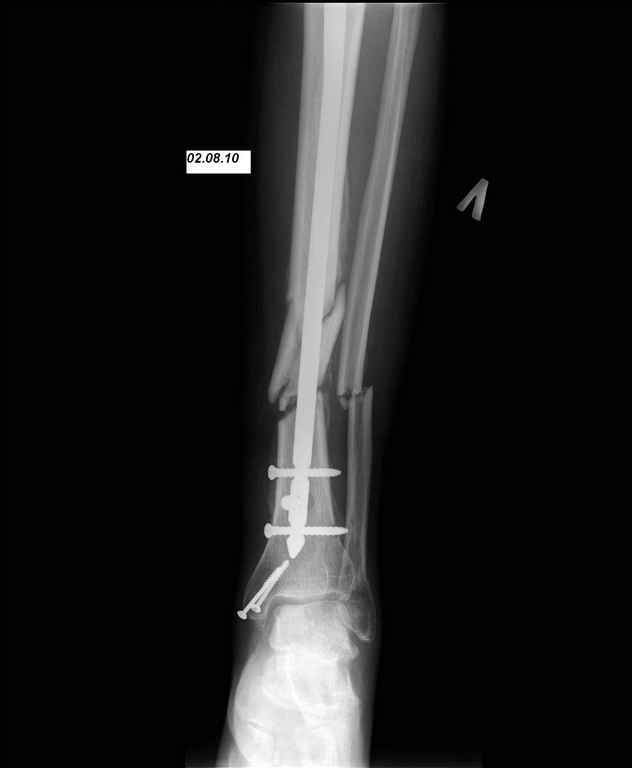

24.03.10 выполнены операции - БИОС перелома большеберцовой кости левой голени (штифт Synthes), остеосинтез перелома внутренней лодыжки левой голени винтами. Послеоперационный период протекал без осложнений. Выписан на 10 сутки. Амбулаторно не наблюдался.

И вот опять объявился. Снимки и фотографии в приложении(первичные потеряны). Около 1 месяца назад появились боли в области нижней трети голени в проекции дистальных блокирующих винтов, передвигался с нагрузкой 50% (сам для себя так решил, сам себе разрешил). Путешествовал по Волгоградской области, обратился к травматологу, со слов перевязывали, лечили антибиотиками. Лучше не стало. Вернулся домой.

Вчера госпитализирован в отделение. Локально умеренный отек, кожная температуа не повышена. По передней поверхности в области дистального блокируюшего винта свищ, скудное гнойное отделяемое, винт удален на перевязке зажимом. «Старый» свищ не функционирует. Взят бак. посев, ждем результат.

Возможности и рассматриваемые варианты дальнейшего лечения: 1. удаление штифта, промывное дренирование, ЧКДО. Ждать сращения. 2. удаление штифта, ДРУ (по Челнокову А.Н.), понаблюдать несколько дней+антибиотики(в\в/в\м, перевязки), временно спейсер?, затем БИОС штифтом с АБ покрытием (есть штифты Synthes, Sanatmetal; по нашему мнению самый отпимальный вариант, НО более взрослые коллеги не поддерживает наших «новаторских» предложений, поэтому опыт штифтования с АБ покрытием небольшой). Варианты типа удалить штифт+гипс или вытяжение не рассматриваем. Подскажите, пожалуйста, какой вариант наиболее предпочтительней. И терзает вопрос, что привело к нагноению/остеомиелиту? Нестабильность? В настоящее время с пациентом проведена беседа, настроен на лечение, регулярное наблюдение, выполнение рекомендаций. Ждем Ваших советов и комментариев. Заранее спасибо.

Здесь в любом случае надо давно делать реостеосинтез, есть очевидная нестабильность. Поскольку пациент не сильно надежный, наверно, лучше бы сделать все в один этап. Удалить, дистрактором восстновить длину и ось, рассверлить мм до 14-15, помыть канал, и заштифтовать гвоздем с покрытием. Взять гвоздь длиннее этого. И для большей стабильности ввести винт(ы) мимо гвоздя.

Во первых штифт тонкий, во вторых коротккий. Не смотря на то что дистальное блокирование выполнено 3 винтами, связь с коротким дистальным отломком получиласть слабоватая если учесть активный образ жизни пациента и его "ненадежность" как выразился Александ Николаевич.

Здравствуйте Алексей Алексеевич. К сожалению, это самый "толстый" штифт который у нас есть (d10), и самый длинный (360мм). Пациент отправился на консультацию и возможное лечение к Александру Николаевичу. Административные барьеры не позволили воплотить в жизнь ни один из предложенных вариантов. Всем спасибо за комментарии и советы.